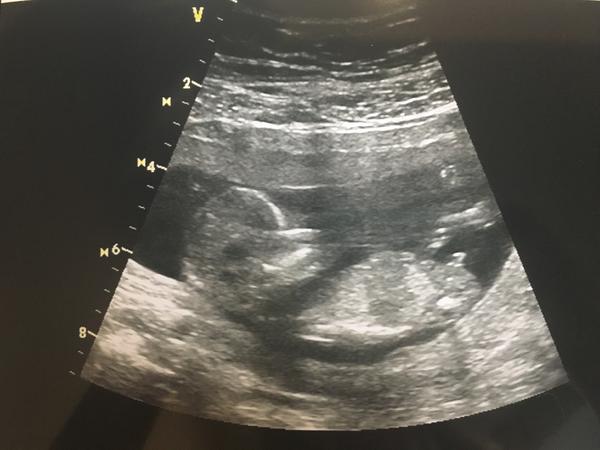

Takhle vypadal prcek minulý týden na screeningu 😊